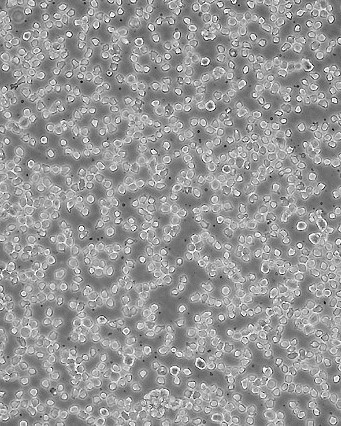

THP-1

THP1; THP 1; THPI; THP-1(ATCC); O-THP-1; Tohoku Hospital Pediatrics-1

90% RPMI-1640+10% FBS

Temperature: 37°C ; Carbon dioxide (CO₂), 5%

悬浮细胞